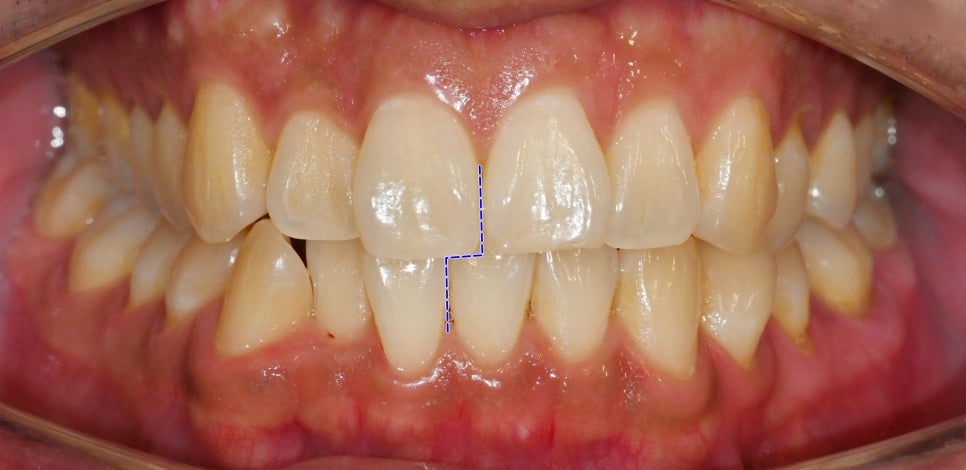

23.11.24

다만, 위 아랫니가 삐뚤빼뚤하고

정중선이 틀어져 있고

맹출 공간이 부족하여

조금 치열이 안 좋습니다.